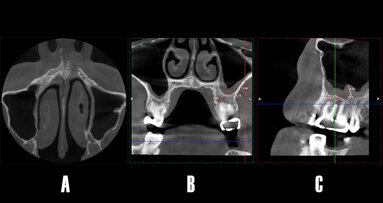

El autor describe las ventajas de la cirugía piezoeléctrica para la extracción atraumática de dientes. Esta tecnología ultrasónica permite realizar también cirugía pre-implantaria de forma segura y precisa, dando como resultado un mejor post-operatorio y una significativa reducción del dolor para el paciente.

La cirugía piezoeléctrica es una técnica desarrollada para el corte de hueso de manera precisa y atraumática basada en microvibraciones ultrasónicas a través del uso de cristales de cuarzo, los cuales vibran al ser estimulados por una corriente eléctrica, generando movimientos oscilantes que son transmitidos al inserto. El inserto tiene una actividad selectiva sobre los tejidos duros calcificados como pueden ser el hueso y el diente, mientras que el tejido blando absorbe la vibración y no produce ningún tipo de daño sobre los tejidos, ventaja importante cuando realizamos osteotomías en áreas afectadas por vasos o nervios o en técnicas de mejora de seno maxilar, donde se respeta la membrana de Schneider, del mismo modo cuando estamos trabajando cerca de la encía o mucosa alveolar.